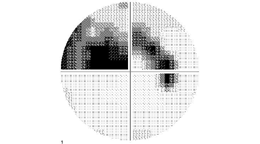

緑内障の視野障害のイメージ

※黒い部分が視野欠損

※眼底写真の所見に一致(上下逆)